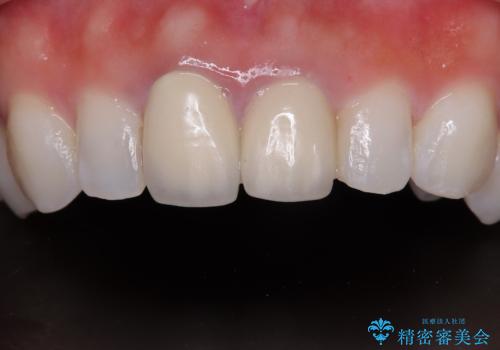

拡大鏡視野下で、被せもの、金属の土台、虫歯を除去し、ファイバーの土台(ファイバーコア)をたてて、オールセラミッククラウンに適した形に整えました。

患者様のご希望で周りの歯も白くしたいとのことでオフィスホワイトニング、ホームホワイトニングで色の調整を行い、色味が落ち着いてから、歯と歯茎の間に圧排糸と呼ばれる糸を入れてシリコーン印象を行いました。

見た目と機能面ともに満足していただきました。